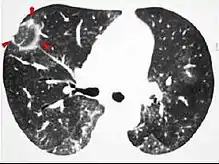

CT image showing halo sign in patient with pulmonary aspergillosis. Note ground-glass opacification surrounding the area of consolidation (circled).

Halo sign

A halo sign refers to a GGO that fills the area around a consolidation or nodule. This is a most commonly seen in various types of pulmonary infections, including CMV pneumonia, tuberculosis, nocardia infection, some fungal pneumonias, and septic emboli. Schistosomiasis, a parasitic infection, also commonly presents with the halo sign. Important non-infectious causes include granulomatosis with polyangiitis, metastatic disease with pulmonary hemorrhage, and some types of idiopathic interstitial pneumonias.[6]